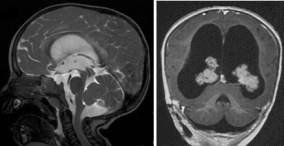

tumeurs du plexus : à gauche, papillome du V4 avec hydrocéphalie tumorale mais non obstructive ; à droite, hyperplasie bilatérale - par hyperproduction de LCS exceptionnellement dans les papillomes du plexus choroïdes, ou les hyperplasies qui sont une hypertrophie bénigne non tumorale.